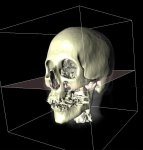

Zusammen mit dem Problem der Visualisierung tritt oft auch das Problem der Segmentierung auf. Unter diesem Begriff versteht man die Erzeugung von inhaltlich zusammenhängenden Regionen durch das Zusammenfassen von Pixeln oder Voxeln entsprechend einem bestimmten Homogenitätskriterium. Ein CT-Voxeldatensatz kann z.B. eine Aufnahme eines menschlichen Kopfes darstellen. Ein Teil dieser Aufnahme besteht aus Knochen, ein Teil des Knochens würde von einem Mediziner als "Unterkiefer" bezeichnet. Beides, sowohl "Knochen" als Oberbegriff als auch "Unterkiefer" als Teilmenge von "Knochen", bezeichnet man als Segment und die (manuelle oder automatische) Erzeugung eines solchen Segments als Segmentierung.